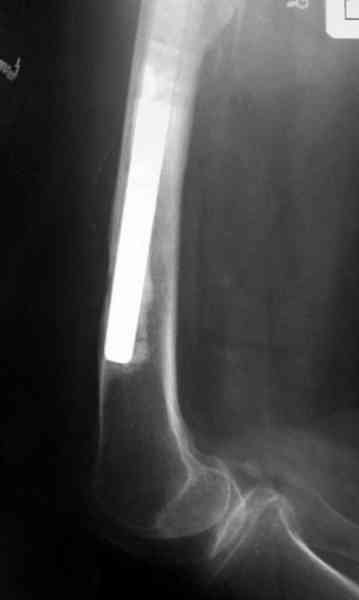

Приглашенный хирург установил ревизионный вариант бедренного компонента без замены ацетабулярного компонента, что осложнилось нагноением и свищами на уровне сустава и средней трети бедра. После двухгодичного безуспешного лечения перевязками и антибиотиками больная обратилась к нам на консультацию.

Повторная операция по удалению тотального протеза с irrigation&debridment, канал после очистки цемента обильно промыт и рассверлен римером.

Приготовлен цемент из расчета: Tobramycin 2.4 g (2 флакона), Vancomycin 2 млн (4 флакона) и 2 упаковки цемента с добавлением дополнительного флакона цементной жидкости.

После обработки ацетабулярного компонента, ещё в мягком цементе в полости вертлужной впадины головкой бедренного компонента сделана выемка для головки, чтобы свежий цемент не прилипал к головке. Головку бедренного компонента завернул обычной стерильной фольгой, которую после образования выемки отлепил от головки.

Для спейсера в бедро использовал старый длинный бедренний компонент меньшего диаметра, облепленный со всех сторон цементом с антибиотиком.

Наглухо ушитая рана с дренажом зажила первично, после чего с больной потерял контакт, и только недавно, через 8 лет я осмотрел её. Она без проблем нагружает на конечность и передвигается с помощью трости. От окончательной операции по реконструкции отказывается, довольная результатом.

Имеются литературные данные, когда спейсер держали не более 6 месяцев, но этот случай бьет все рекорды, может быть для наших людей, обременных финансовыми трудностями, нужна другая шкала оценки сроков нахождения спейсеров.

№3-6 снимки с осложнением

и последние снимки.